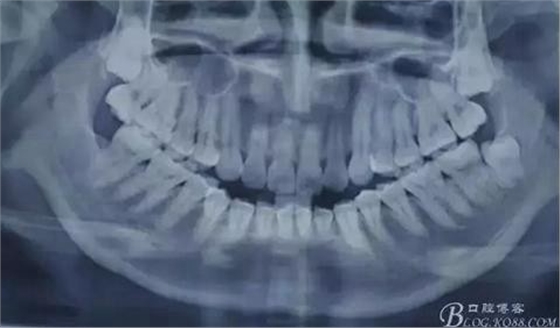

圖1.術(shù)前全景片影像檢查:18、28高位近中阻生,牙冠均緊鄰17、27牙頸部,牙根近鄰上頜竇。